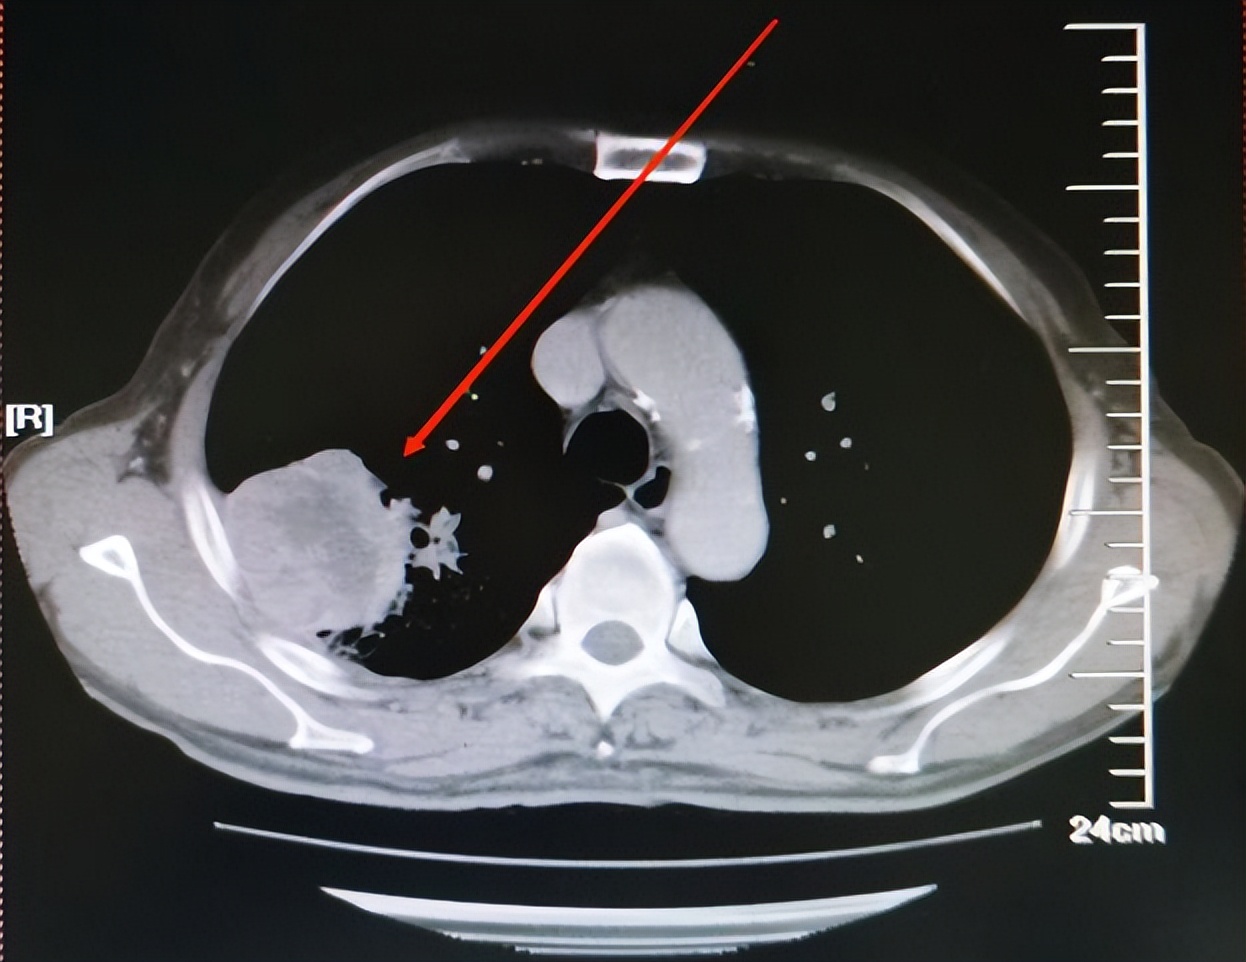

胸部CT提示右上肺叶肺癌待排,双肾上腺多发转移可能(见图1)。他儿子拿着结果来找我的时候情绪很是激动,说不管用什么办法,花多少钱都要治好他父亲,年轻时就顾着挣钱了,10几年都没有回去看看老父亲,好不容易能让他享享福了,却查出来了这个病。

图片来源 :讲述者提供